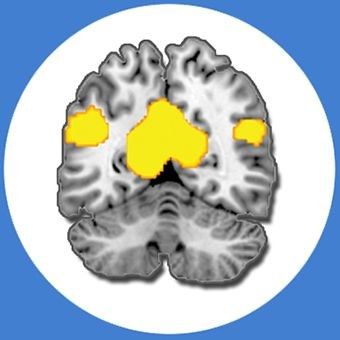

We investigate these questions using neuroimaging, cognitive and neuropsychological methods, working with healthy young and older adults as well as people with memory difficulties due to depression and dementia.